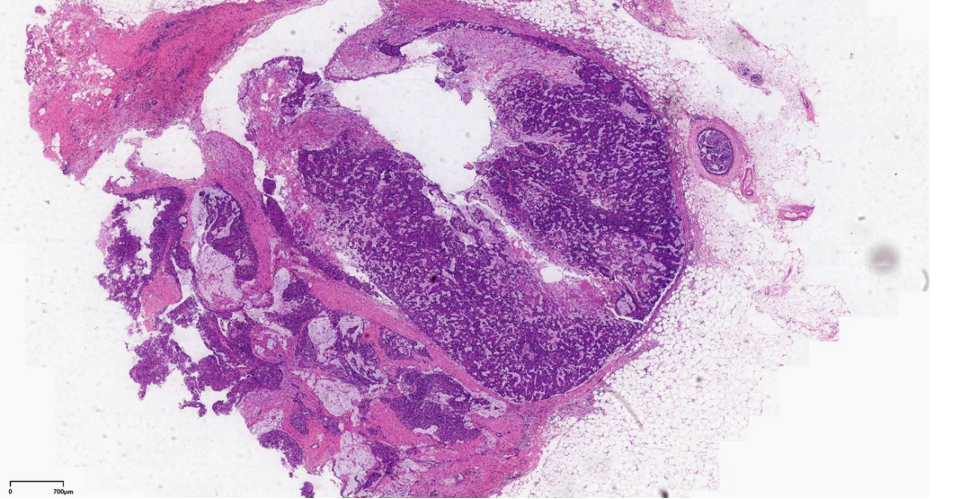

右乳肿块:淡黄色组织一块约直径1.9cm,切面见直径1.6cm的灰白灰红色结节,界清,质中。

最终诊断:(右)乳腺实性乳头状癌,伴浸润,浸润成分为富于细胞的粘液癌。

左乳肿物:灰黄色组织一块约5.4*4.1*3.9cm,切面见直径1.9cm的暗红灰白区域,质中,界不清。

最终诊断:浸润性实性乳头状癌,部分为粘液癌。

结构特点:轮廓清楚的实性结节纤细的血管轴心。

DCIS样,界限清楚、多个、膨胀性结节状

原位SPC:轮廓光滑的圆形结节结节周围无促结缔组织增生结节周围肌上皮可有可无

浸润癌两种浸润方式

1、浸润性实性乳头状癌:保留实性乳头状结构,体积大的团巢,轮廓不规则,间质促纤维反应,肌上皮缺失,原位SPC背景

2、实性乳头状癌伴浸润:轮廓圆滑的结节,伴有浸润性成分,包括粘液癌,NET,浸润性癌(NST)

SPC+富于细胞的黏液癌

浸润性SPC